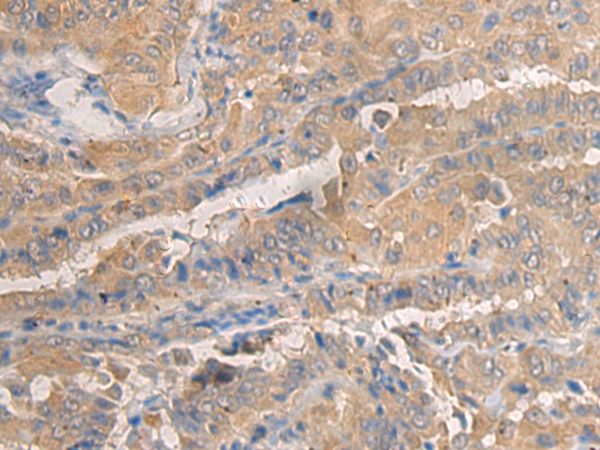

The image is immunohistochemistry of paraffin-embedded Human thyroid cancer tissue using (AGAP3 Antibody) at dilution 1/25.

The image is immunohistochemistry of paraffin-embedded Human breast cancer tissue using (AGAP3 Antibody) at dilution 1/25.